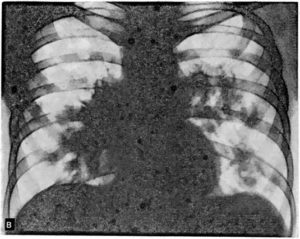

Рентгенологические данные могут иметь определенные различия и зависят от формы и стадии болезни:

- В стадии инфильтрации над поверхностью легких определяется снижение прозрачности легочного рисунка, затем плотность затенения возрастает, и становится виден инфильтрат неправильной формы с размытыми контурами и радиальной тяжистостью по периферии.

- Стадия абсцедирования характеризуется наличием очагов деструкции в пораженном легком с перифокальным воспалением и усилением легочного рисунка в здоровом легком.

- Нередко после прорыва абсцесса в паренхиме легких формируются плевролегочные полости с горизонтальным уровнем жидкости.

Рентгенологическое исследование в ранней стадии выявляет очаговые инфильтраты вокруг бронхов и сосудов, увеличение медиастинальных лимфатических узлов и содружественное поражение ребер или позвонков; характерно уплотнение плевры. Процесс может ограничиваться одним сегментом или захватывать целую долю. Течение болезни длительное, при отсутствии лечения развиваются кахексия и анемизация больных.